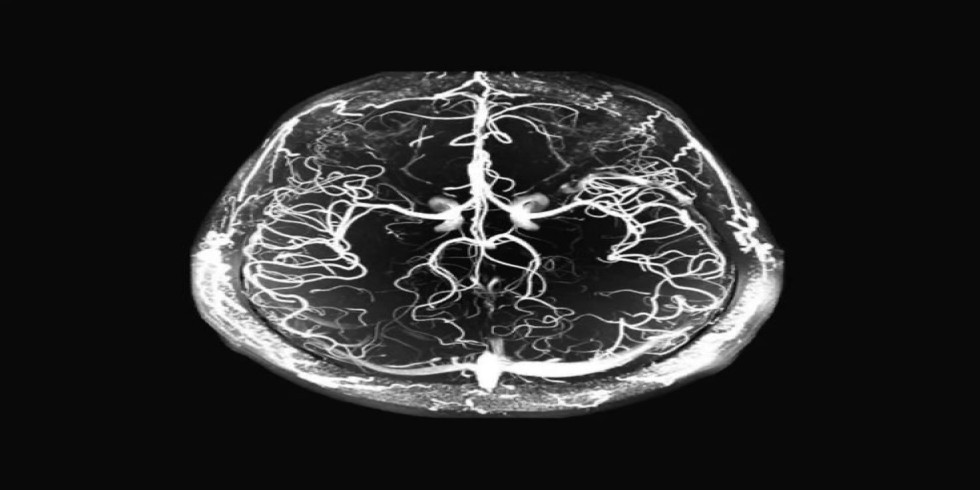

Brain tumors